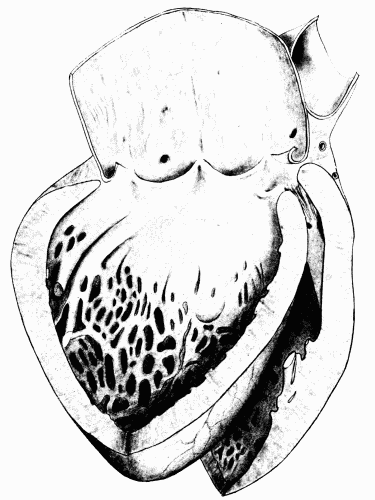

Fig. 11.—Enormous hypertrophy of left ventricle probably due to prolonged increased peripheral resistance. Note that the whole anterior surface of the heart is occupied by the left ventricle. The right ventricle does not appear to be much affected. × ⅔. Fig. 11.—Enormous hypertrophy of left ventricle probably due to prolonged increased peripheral resistance. Note that the whole anterior surface of the heart is occupied by the left ventricle. The right ventricle does not appear to be much affected. × ⅔.